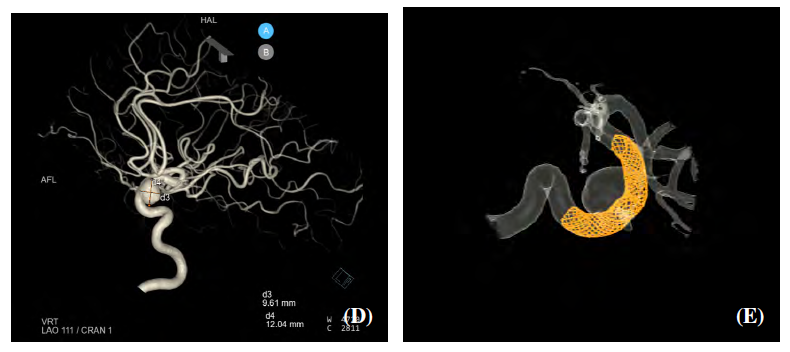

As part of a joint proof-of-concept project, the case of a female patient with an aneurysm in one of the major cerebral arteries was analysed. Computational Fluid Dynamics (CFD) served as a supporting tool in this study, enabling the quantification of parameters such as shear stress, flow oscillations, and blood residence time in a realistic 3D model of the blood vessels created from angiographic data. Based on these calculations, it was possible to compare selected haemodynamic characteristics before and after the procedure.

The simulations were performed on the Karolina supercomputer, which is operated by IT4Innovations National Supercomputing Center. Experts from the IT4Innovations Parallel Algorithms Research Lab provided the methodology, software solutions, analysis, and visualisation. The results offered a more detailed insight into how the treatment affected the haemodynamics in the aneurysm region and provided the clinical team with additional quantitative data to interpret the findings.

Visualisation of the patient's blood vessels